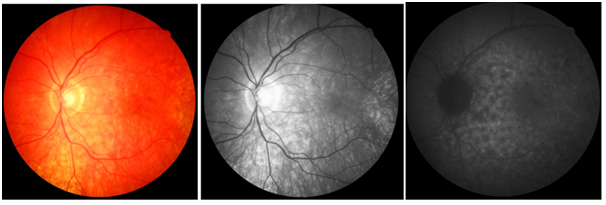

Laboratory tests showed the following results: complete blood count without changes, serology for non-reactive HIV, VDRL 1/128, toxoplasmosis IgG positive (185.0) and IgM negative (0.43), serologies for hepatitis B and C negative, FAN negative and negative rheumatoid factor. Ultrasonography was then performed in both eyes, which showed the presence of multiple pockets of serous retinal detachment with a macula glued to the right eye; and multiple pockets of serous retinal detachment, with macular edema in the left eye. With the diagnosis of Vogt-Koyanagi-Harada syndrome closed, treatment with oral prednisone 1 mg / kg was initiated, in addition to maintaining 1% prednisolone eye drops at weekly weaning. Two weeks after the beginning of oral immunosuppressive therapy, there was an improvement in visual acuity, which presented, with correction, in DO, 20/30 and in LEFT EYE, 20/40; in addition to reduction of retinal edema. Intraocular pressure using Goldmann's tonometry, OD 24mmHg and LEFT EYE 26mmHg, and associated brimonidine eye drops with timolol of 12 / 12h in both eyes (BE). In subsequent consultations, the patient presented negative VDRL after treatment for syphilis and control of intraocular pressure using hypotensive eye drops. Slow weaning from oral prednisone was carried out over the course of a year and maintained at 20 mg / day with stabilization of visual acuity at 20/20, with correction, in both eyes. One year after the onset of the condition, the patient presented to the retinography the presence of a "sunset" image in the right eye (Figure 3a) and in the left eye (Figure 3b)  Angiography showed the presence of hyperfluorescent lesions due to a window defect, due to the mobilization area and atrophy of the retinal pigment epithelium, seen during the examination, both in the left eye (Figure 5a) and in the right eye (Figure 5b). In an attempt to completely withdraw oral medication with slow weaning, visual loss of three lines was observed in the Snellen table in RIGHT EYE (20/40) and LEFT EYE remained stable at 20/20. Thus, a dose of 20 mg/ day of oral prednisone was maintained for two months, with slow weaning to 5 mg/ day, but again there was a worsening of VA (RIGHT EYE: 20/40 and LEFT EYE: 20/30). Thus, it was decided to suspend oral prednisone at 20mg / day and start injectable treatment with adalimumab. The patient is waiting for the medication to be released by the Unified Health System.

Figure 4 Optical coherence tomography.

Two months after the onset of the condition, dermatological changes may also appear, constituting the convalescent. They are poliosis, vitiligo and alopecia. However, the study patient did not present any evident dermatological symptoms. The characteristic ‘’ sunset ’’ eye fundus was described in the assessment made one year after the onset of the condition.15 The recurrent chronic phase may or may not occur. When present, recurrent retinal detachments, formation of retinal neovascular membranes, glaucoma and cataracts occur. These complications occur in about 1/3 of the patients.14,15 Our patient progressed well with treatment and did not show recurrence symptoms, despite the difficulty in weaning from therapy and staying on medication for more than a year. Regarding the most used complementary exams, in the OCT the most common findings are folds and serous detachment of the retinal pigment epithelium (RPE), presence of septa and areas of subretinal fluids, with macular area thickness varying between 700-900 microns ( 12.16). Ocular ultrasound can show choroidal thickening, papilla edema and areas of serous retinal detachment. Regarding fluorescein angiography, fluorescein pooling can be seen in areas of serous detachment and leakage of the optical disc.12 In the patient, the OCT (one year after the onset of the condition) showed an increase in foveal thickness and cysts in the internal retinal layers; on ultrasound, we see the presence of multiple pockets of serous retinal detachment; and in fluorescein angiography, we observed hyperfluorescent areas by window and pooling defect. Such findings corroborate the evidence in the literature cited above. Treatment must be early and it is done with the use of corticosteroids and immunomodulatory drugs to control the effects produced by autoimmunity and reduce damage.1 After the symptoms improve, the treatment should be discontinued slowly, from 3 to 6 months, and should be maintained for about a year in case of recurrences. In severe forms of the disease, there is benefit in the triple use of immunosuppressive therapy, which consists of prednisolone, azathioprine and cyclosporine, simultaneously.1 The inflammatory and exudative retinal process can improve with the application of intravitreal triamcinolone injection.17 Some studies suggest that sub-tenonian injection of triamcinolone should be an initial treatment for relapse of VKH in pregnant women.18 The study patient improved only with prolonged use of oral and topical corticosteroids, not requiring immunomodulatory therapy. Poor access to immunomodulatory medications through the Unified Health System also restricts treatment to corticosteroids. The main complications of VKH syndrome are secondary glaucoma, cataracts, choroidal neovascularization and subretinal neovascular membrane in the recurrent chronic phase.14,19 The study patient did not have any of these complications. Chronicity of the condition usually occurs when there is a delay in diagnosis, often due to ignorance of the initial clinical manifestations of the disease. The time between the onset of symptoms and the institution of immunosuppressive therapy is essential for final visual acuity, influencing the prognosis of the disease.